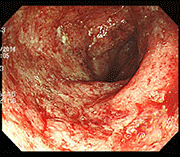

潰瘍性大腸炎前後の粘膜回復

腸粘膜のひどい炎症、発赤、潰瘍が治まり、滑らかで健康な状態に回復した事例です。

事例 2

治療前 治療前 腸内粘膜写真

治療後 治療後 腸内粘膜回復写真